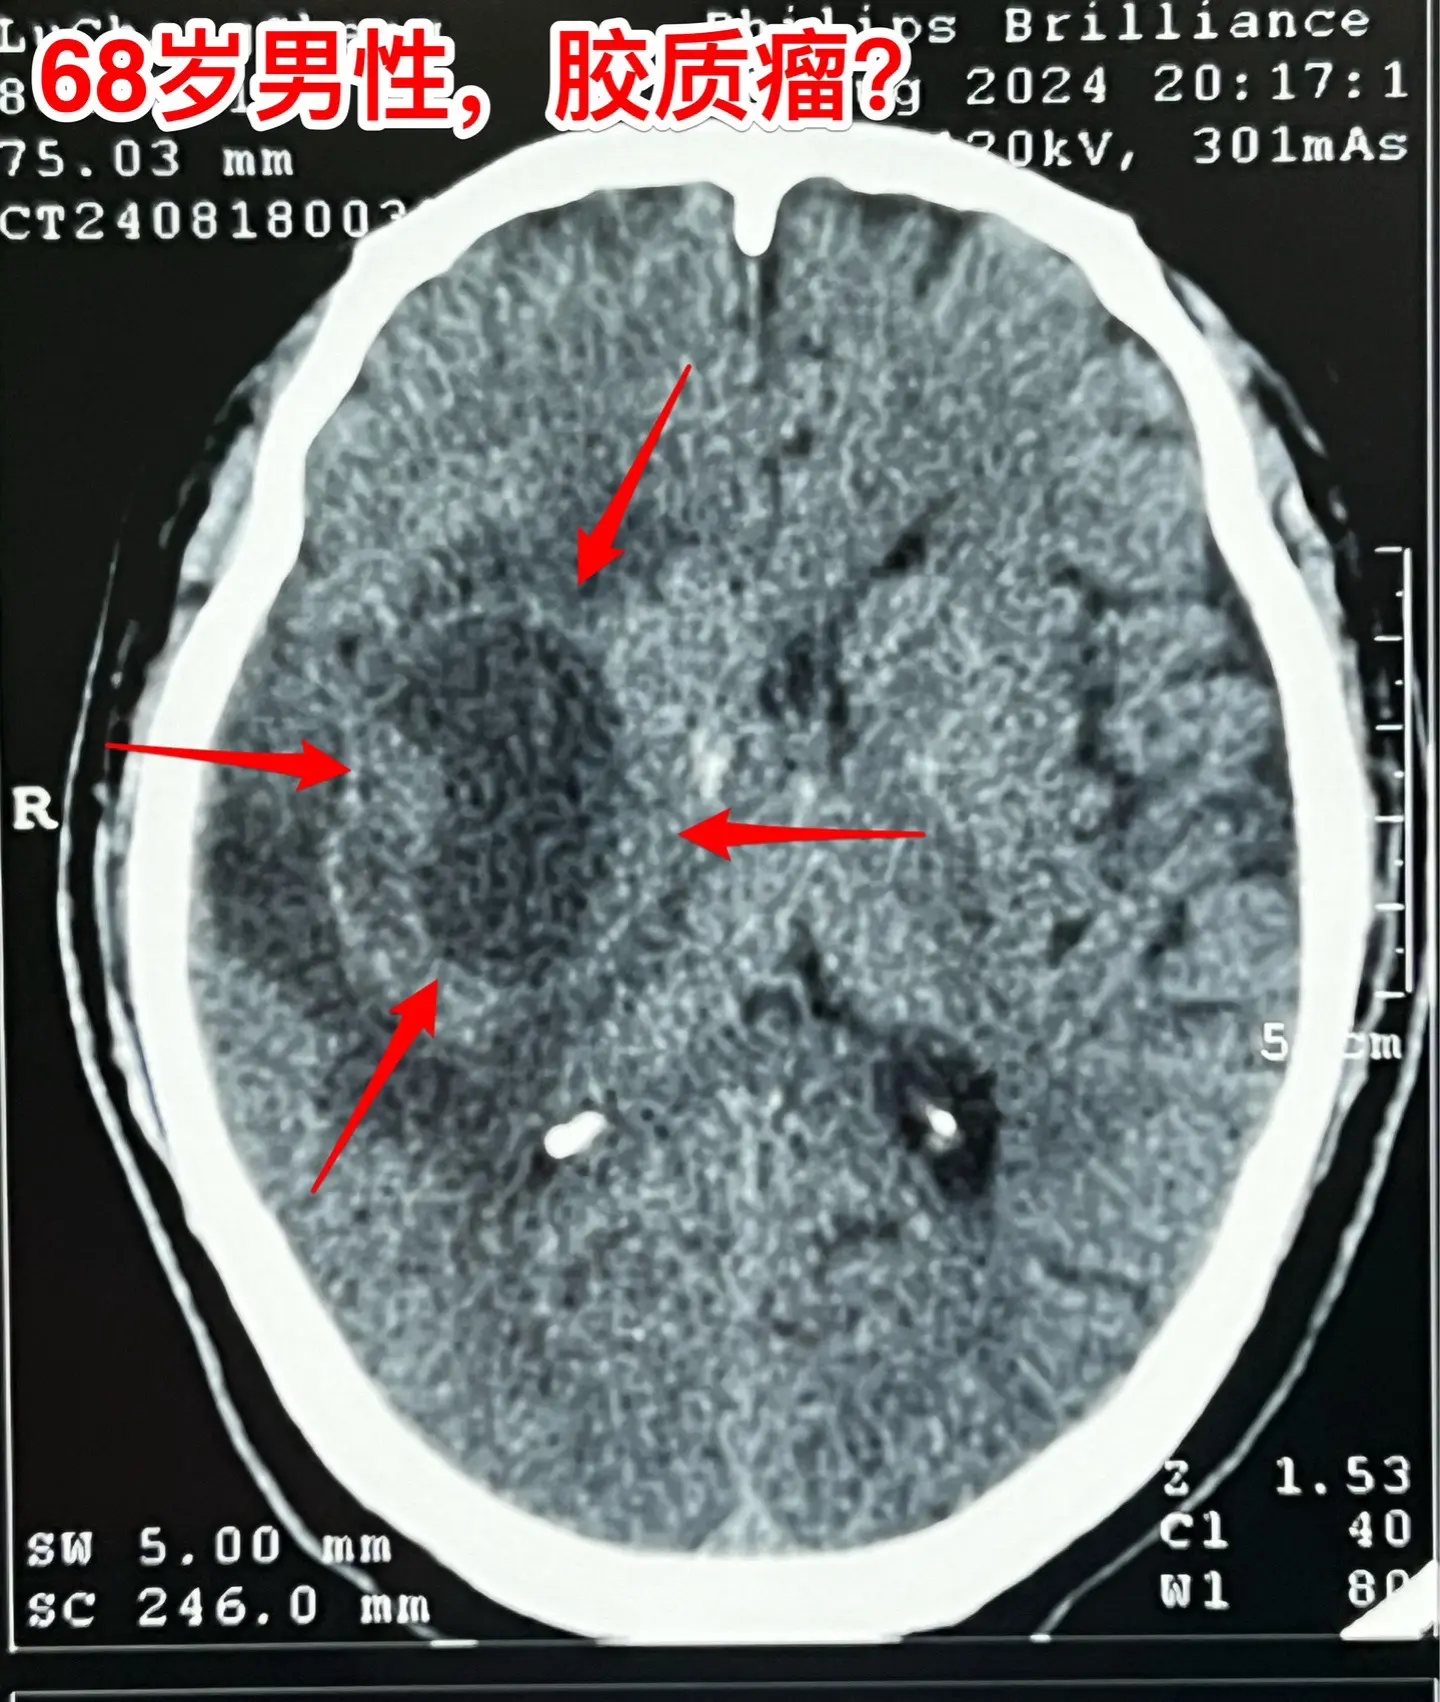

老人擀饺子皮的质量下降了,原因是什么?68岁的唐山市老人,擅长擀饺子皮、包饺子,平时擀出的饺子皮中央稍厚、四周均匀薄。然而近期他擀出的饺子皮形态不规整,厚薄一致,与平时的水准大相径庭,是什么原因呢?而且家人发现他穿鞋系鞋带动作又慢又笨拙!跟平时完全不一样。 病人的女儿在北京当医生。 到医院去检查脑部磁共振就发现脑部长了一个瘤。这个瘤位于左侧颞叶-基底节区,压迫内囊区域,虽然没有造成明显的偏瘫症状,但是也造成了左侧上下肢活动不灵活。 8.16到我这里来住院,8.23作了手术,术中的快速冰冻病理提示高级别神经上皮肿瘤,即胶质瘤的一种。 手术后老人没有出现明显的偏瘫症状。 这样的肿瘤单纯作手术是不够的,还需要作放疗、化疗。